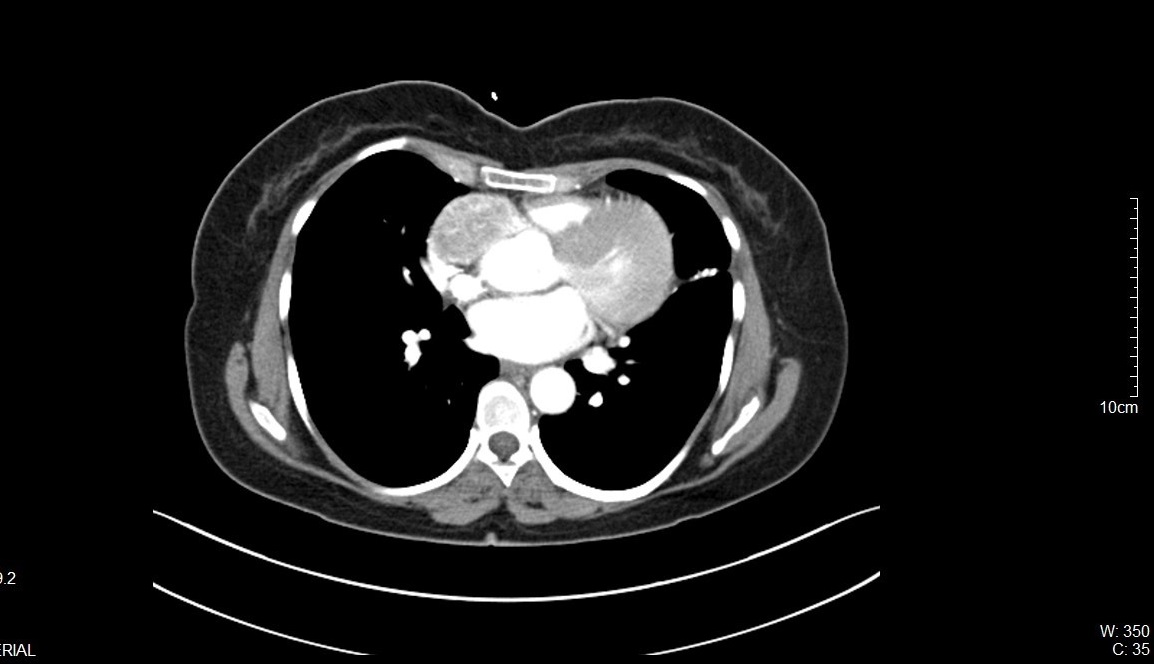

On further evaluation, the patient’s echocardiogram showed a 4.5 x 4.3 cm cystic tumor in the right atrium, hypertrophied obstructive cardiomyopathy with moderate left ventricular outflow tract obstruction, and good left ventricular function. She also underwent computed tomography (CT) and magnetic resonance imaging (MRI) of the chest, which revealed a neoplastic mass lesion, most likely right atrial myxoma.

Mediastinal paragangliomas are diagnosed by measuring urinary catecholamines and their metabolites, metanephrines and vanillylmandelic acid. Tumor localization is done with the help of CT, I-MIBG scintigraphy, and MRI. Because of the high vascularity of these lesions, contrast medium administration enhances CT.